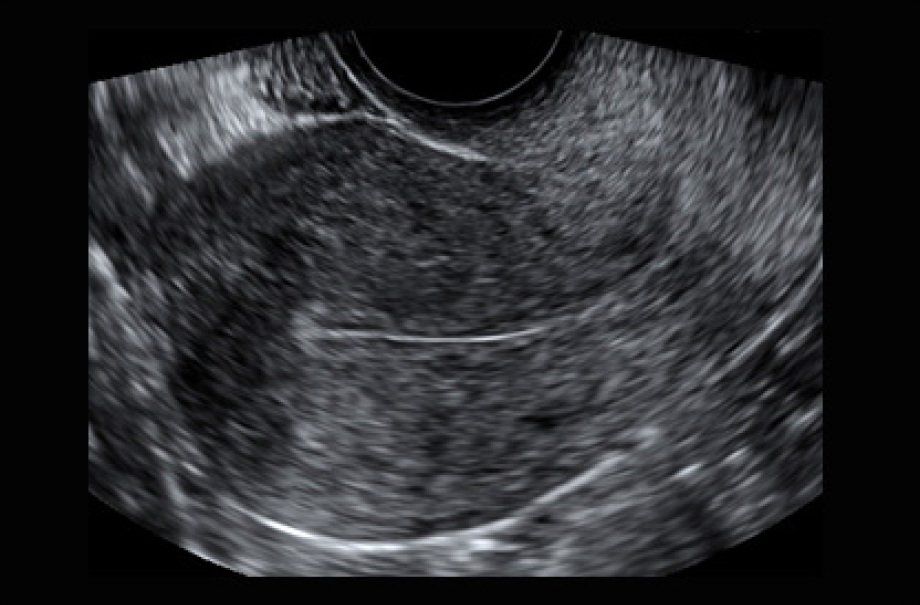

- Transvaginal Scan

- The scan provides detailed images which help to determine if the pelvic organs are normal or have abnormalities such as: